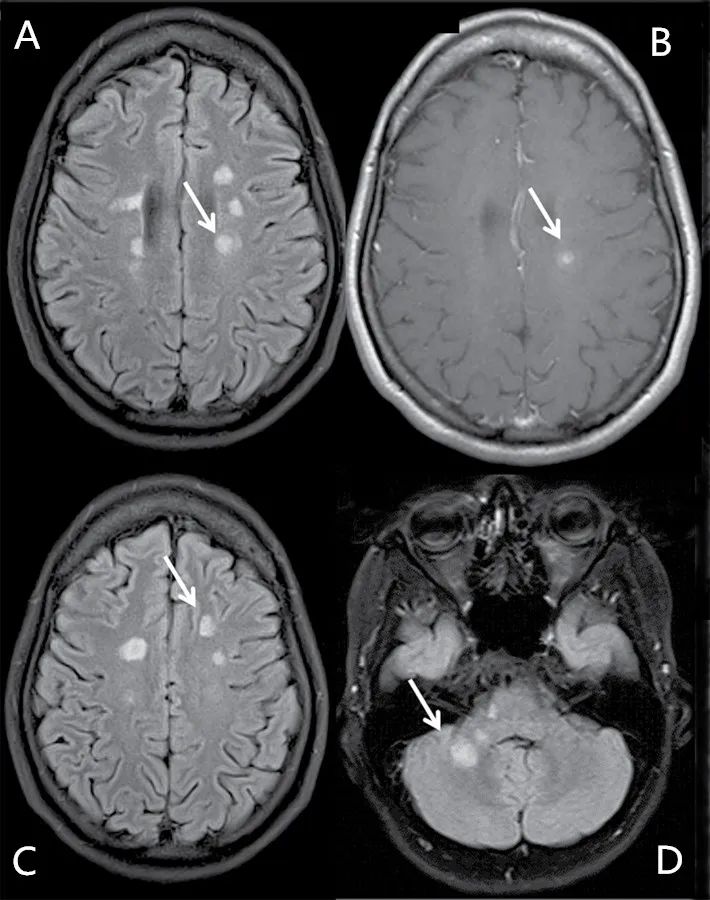

脑MRI通常表现为特征性部位的多灶性T2高信号脑白质病变,包括脑室周围(含胼胝体)、近皮层区域(毗邻大脑皮层)、幕下区域。在T1加权像上,病变可能出现低信号的表现(即所谓的“黑洞”)。脊髓损伤则发生在80%~90%的MS患者和一半的CIS患者,最常见于颈椎。病变延伸超过一个或两个椎骨段,并且经常偏离中心,邻接软膜表面。脑和脊髓的病变在钆增强扫描后可能强化(图)。

图1 MS的典型脑和脊髓病变(箭头显示病变位置) A、B:轴位MRI扫描显示脑室周围多发病变,其中一个病灶增强扫描可见强化;C:显示近皮层区域病变;D:显示幕下病变;E、F、G、H:矢状位和轴位扫描显示颈髓病变,增强扫描可见强化。